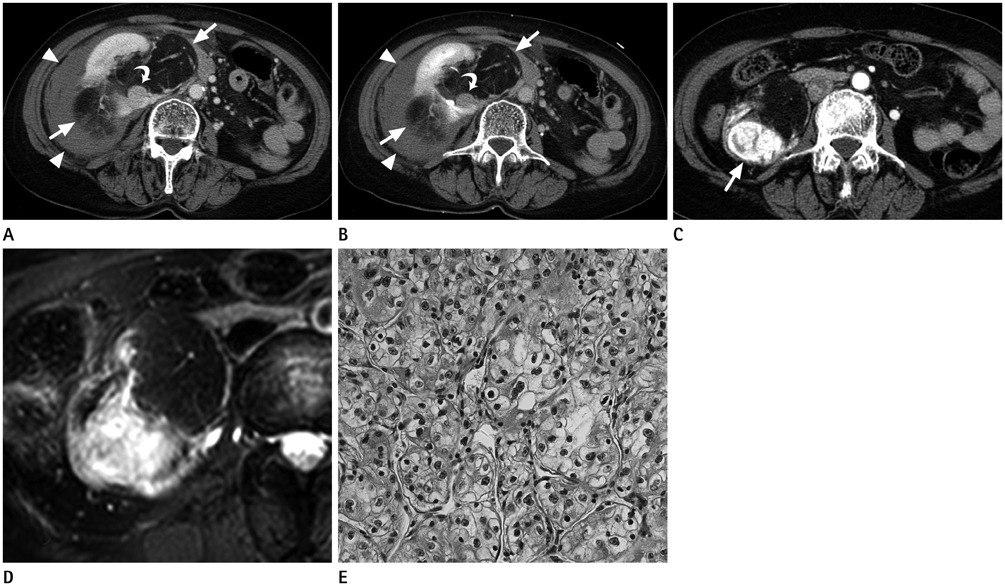

Concurrent Renal Angiomyolipoma and Renal Cell Carcinoma: Report of Two Cases

- Concurrent renal cell carcinoma (RCC) and angiomyolipoma (AML) is a very rare condition, especially in patients without underlying tuberous sclerosis. We present three patients with concurrent RCC and AML in the ipsilateral kidney. Concurrent RCC is difficult to differentiate radiologically from a non-fatty component of an AML because they share several imaging findings. However, several noticeable radiologic features are helpful in the diagnosis of suspected cases. This report of two cases highlights the radiologic features that distinguish RCC from non-fatty components of AML.